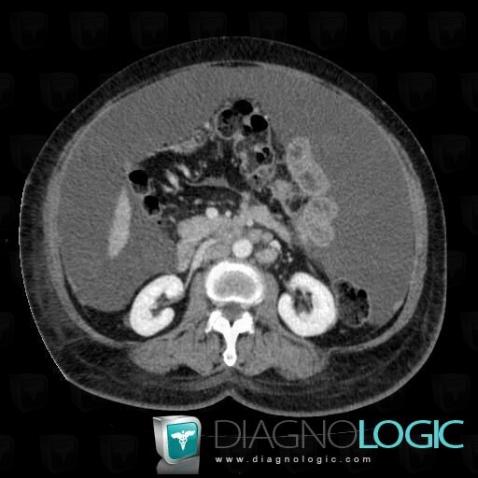

Ascite , Mésentère / Péritoine, Scanner

Voici les informations spécifiques à l'image clé ci dessus:

- Diagnostic Ascite , Localisation(s) Mésentère / Péritoine, comportant les gammes Pathologie du péritoine